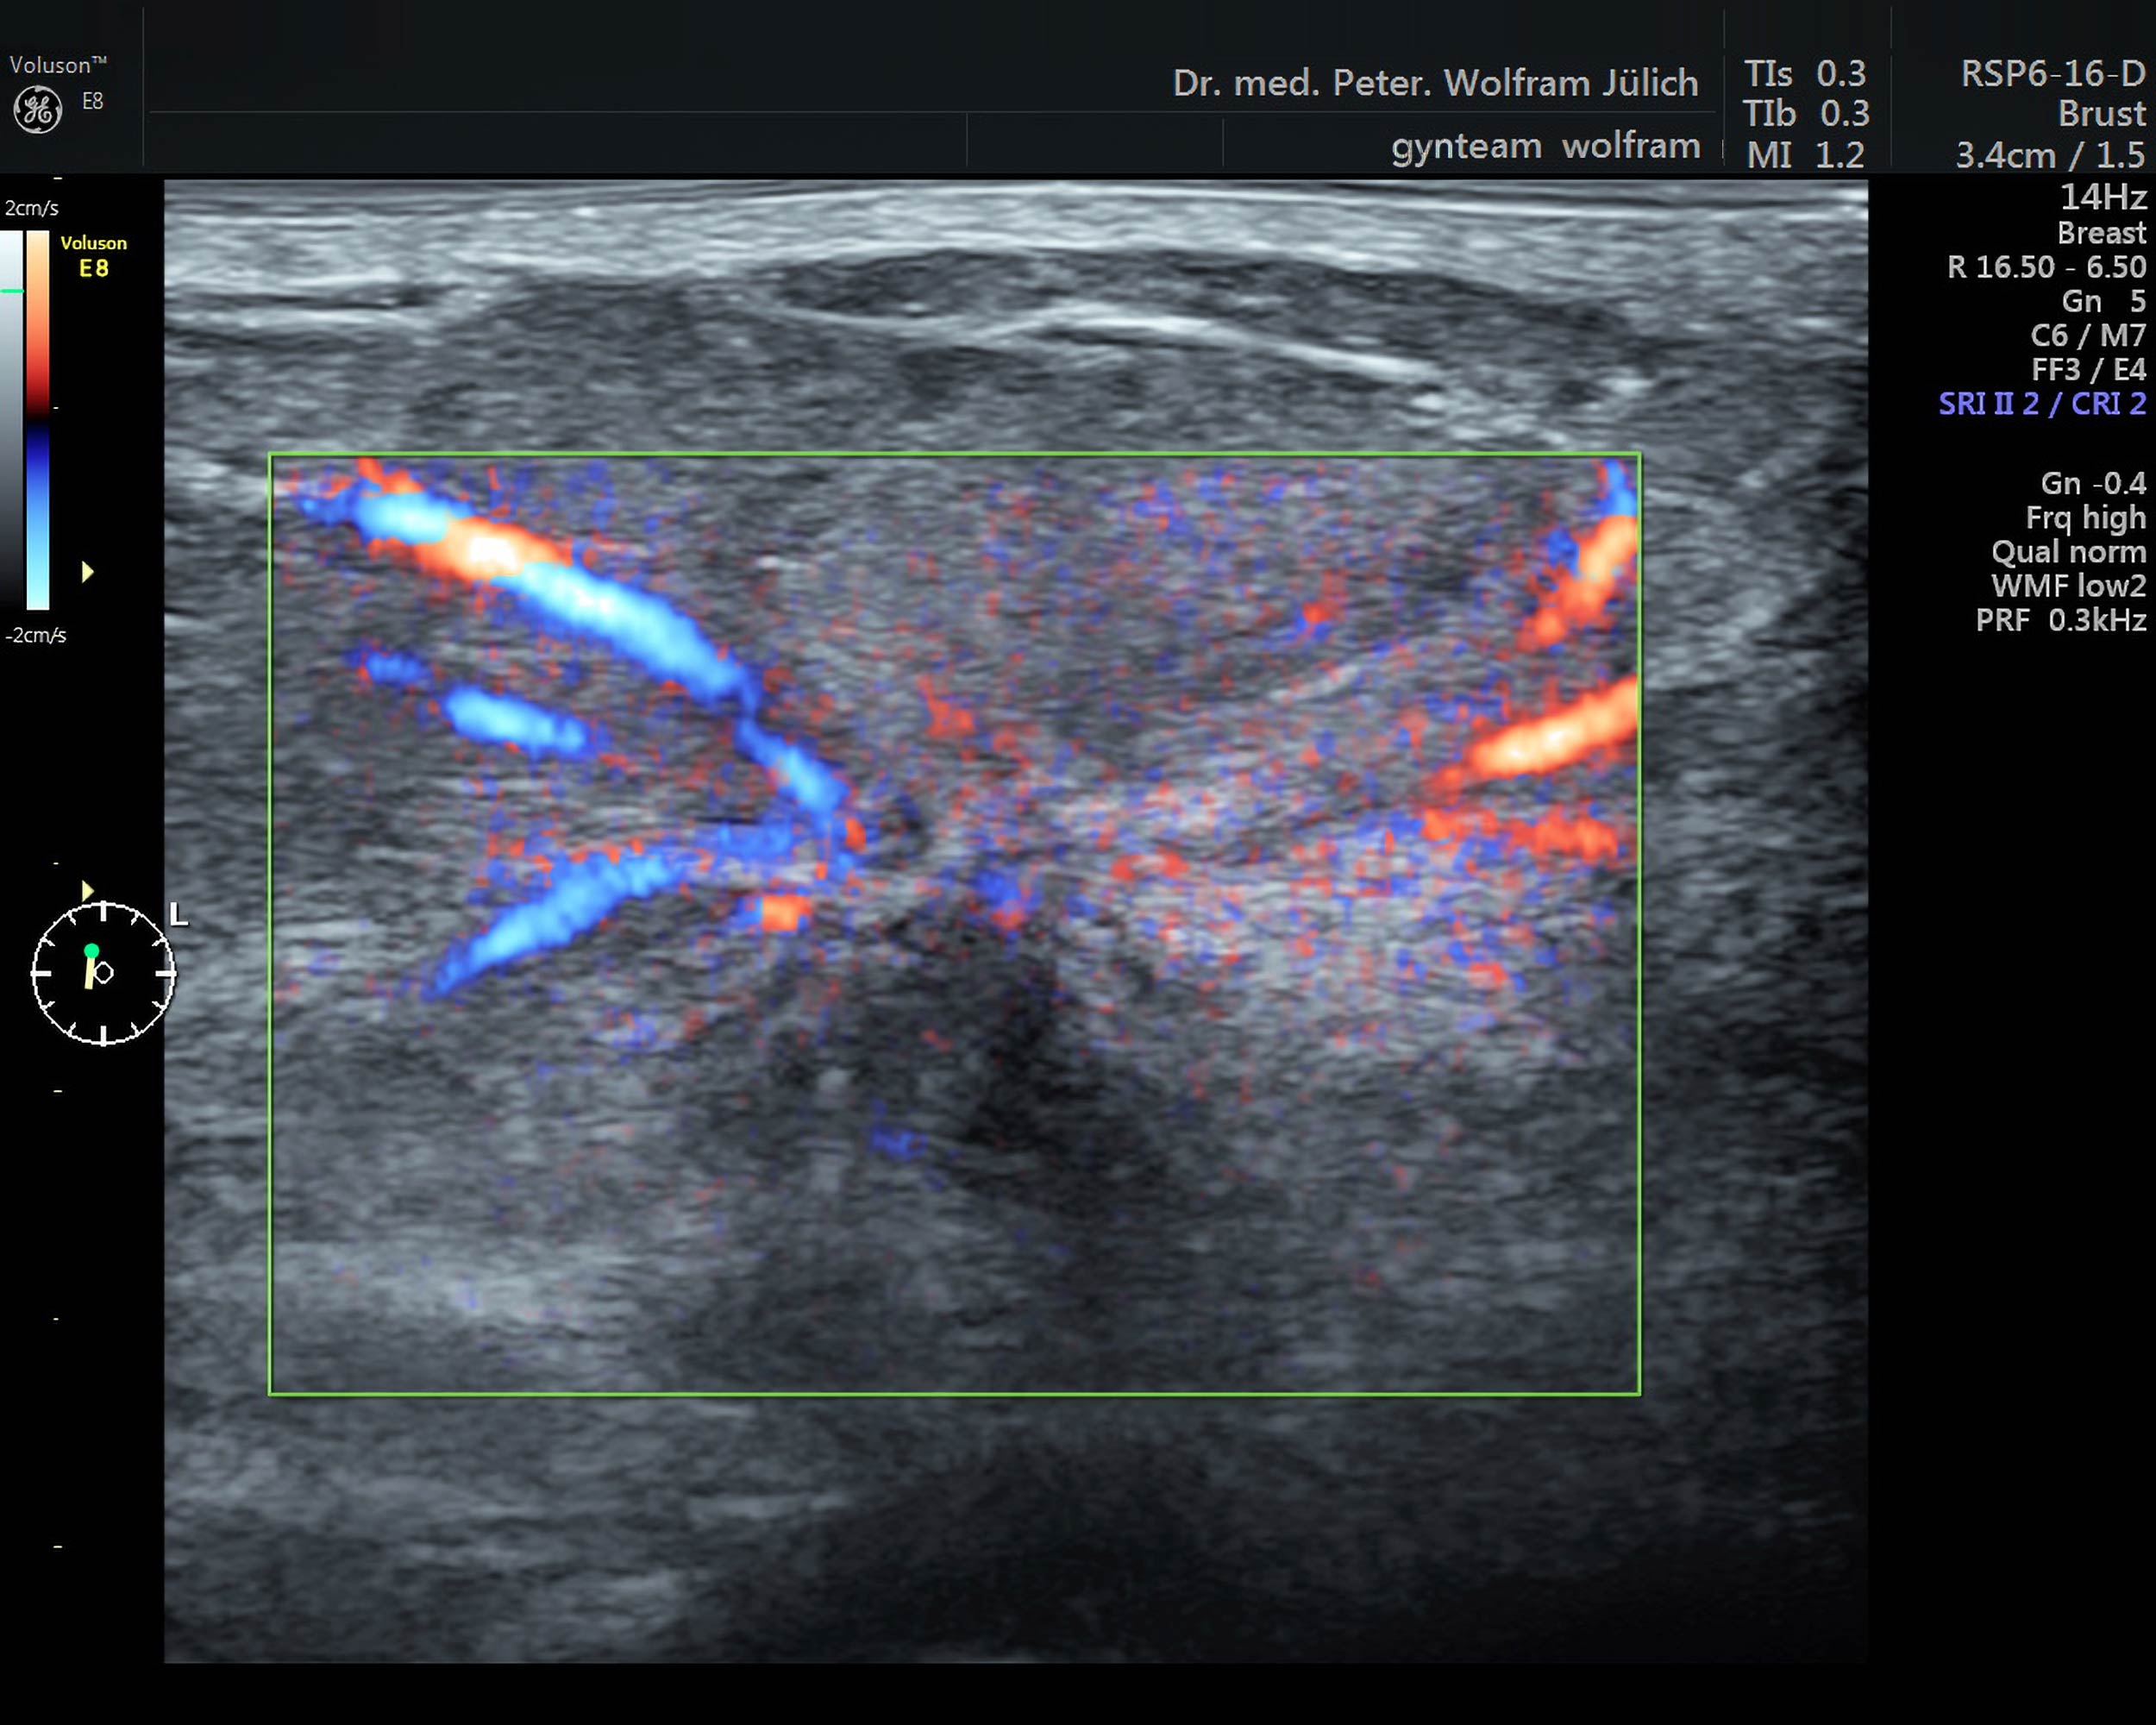

In unseren Praxisräumen nutzen wir ein hochmodernes Ultraschallgerät der neuesten Generation der Voluson-Serie. Es bietet neben einem ultrahochauflösenden Schallkopf  folgende zusätzliche Techniken an::

• 3D-Darstellung mit der Option der Abbildung von Schnittbildern in allen drei Ebenen

• Dopplersonographie (Darstellung von Blutströmen)

• Elastographie (Sichtbarmachung der Gewebekonsistenz)

Diese Zusatztechniken haben eine immer exaktere Abgrenzung zwischen gut- und bösartigen Tumoren ermöglicht.